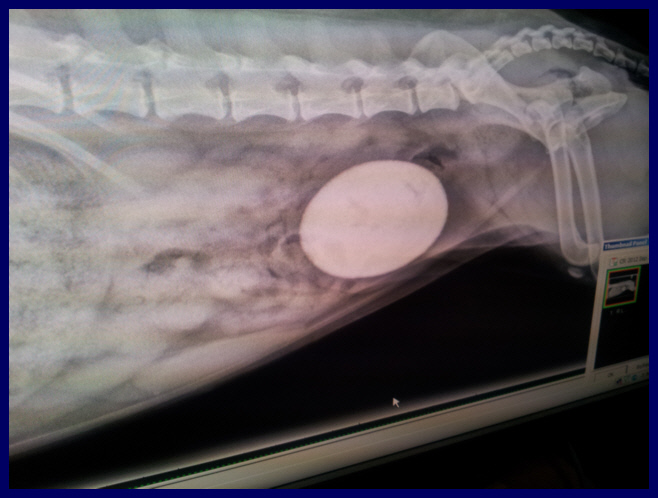

Oh dear. This is upsetting to see, but please

know that they are

both doing well, now.

But man, what the

physical pain they have

had to endure is

really hard to grasp.

We knew that Nellie

had "bladder

issues",

but we did NOT know

that THIS was lurking

inside of her body.

You are looking at a bladder stone that was

the size of a LEMON according to the vet.

It was the largest one they have ever seen.

It was removed yesterday.